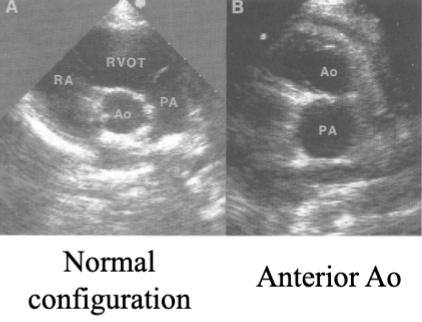

Transposition of Great Vessels (TGV)(TGA)(TOGV)

Dx when the Ao is anterior to the Pulm A

PSAX

2 types of TOGV:

D-Transposition

D = dextro

latin for “right”

L-Transposition

L = levo

latin for “left”